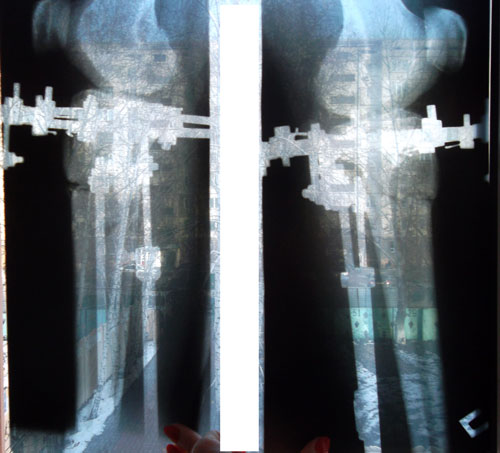

Это мои ножки. Сегодня 5 день. До сих пор не верю, что это происходит со мной. Как будто это сон. У меня двое маленьких детей, быт, куча дел, все не решалась, все думала как я их оставлю, как они без меня. Но все таки решилась! Ура! Я рада, что приближаюсь к своей мечте! Терпения, конечно, надо немалого, но мысль о ровных красивых ножках дает столько сил. Нас в данный момент двое, я и loginza499, у нее сегодня 18 день, исходники наши почти похожи, только ножки у нее худее. У нее уже заканчиваются Крутки и я вижу ее результат, ножки реально стали ровными. Я рада за нее и ее результат мне придает столько сил и уверенности. А в общем что касается больницы, персонала, то мне все нравится. Все вежливые, спокойные. Тут бессменная, незаменимая Маришка, молодец! Во всем поможет, позаботится. Кто лежал, знают.